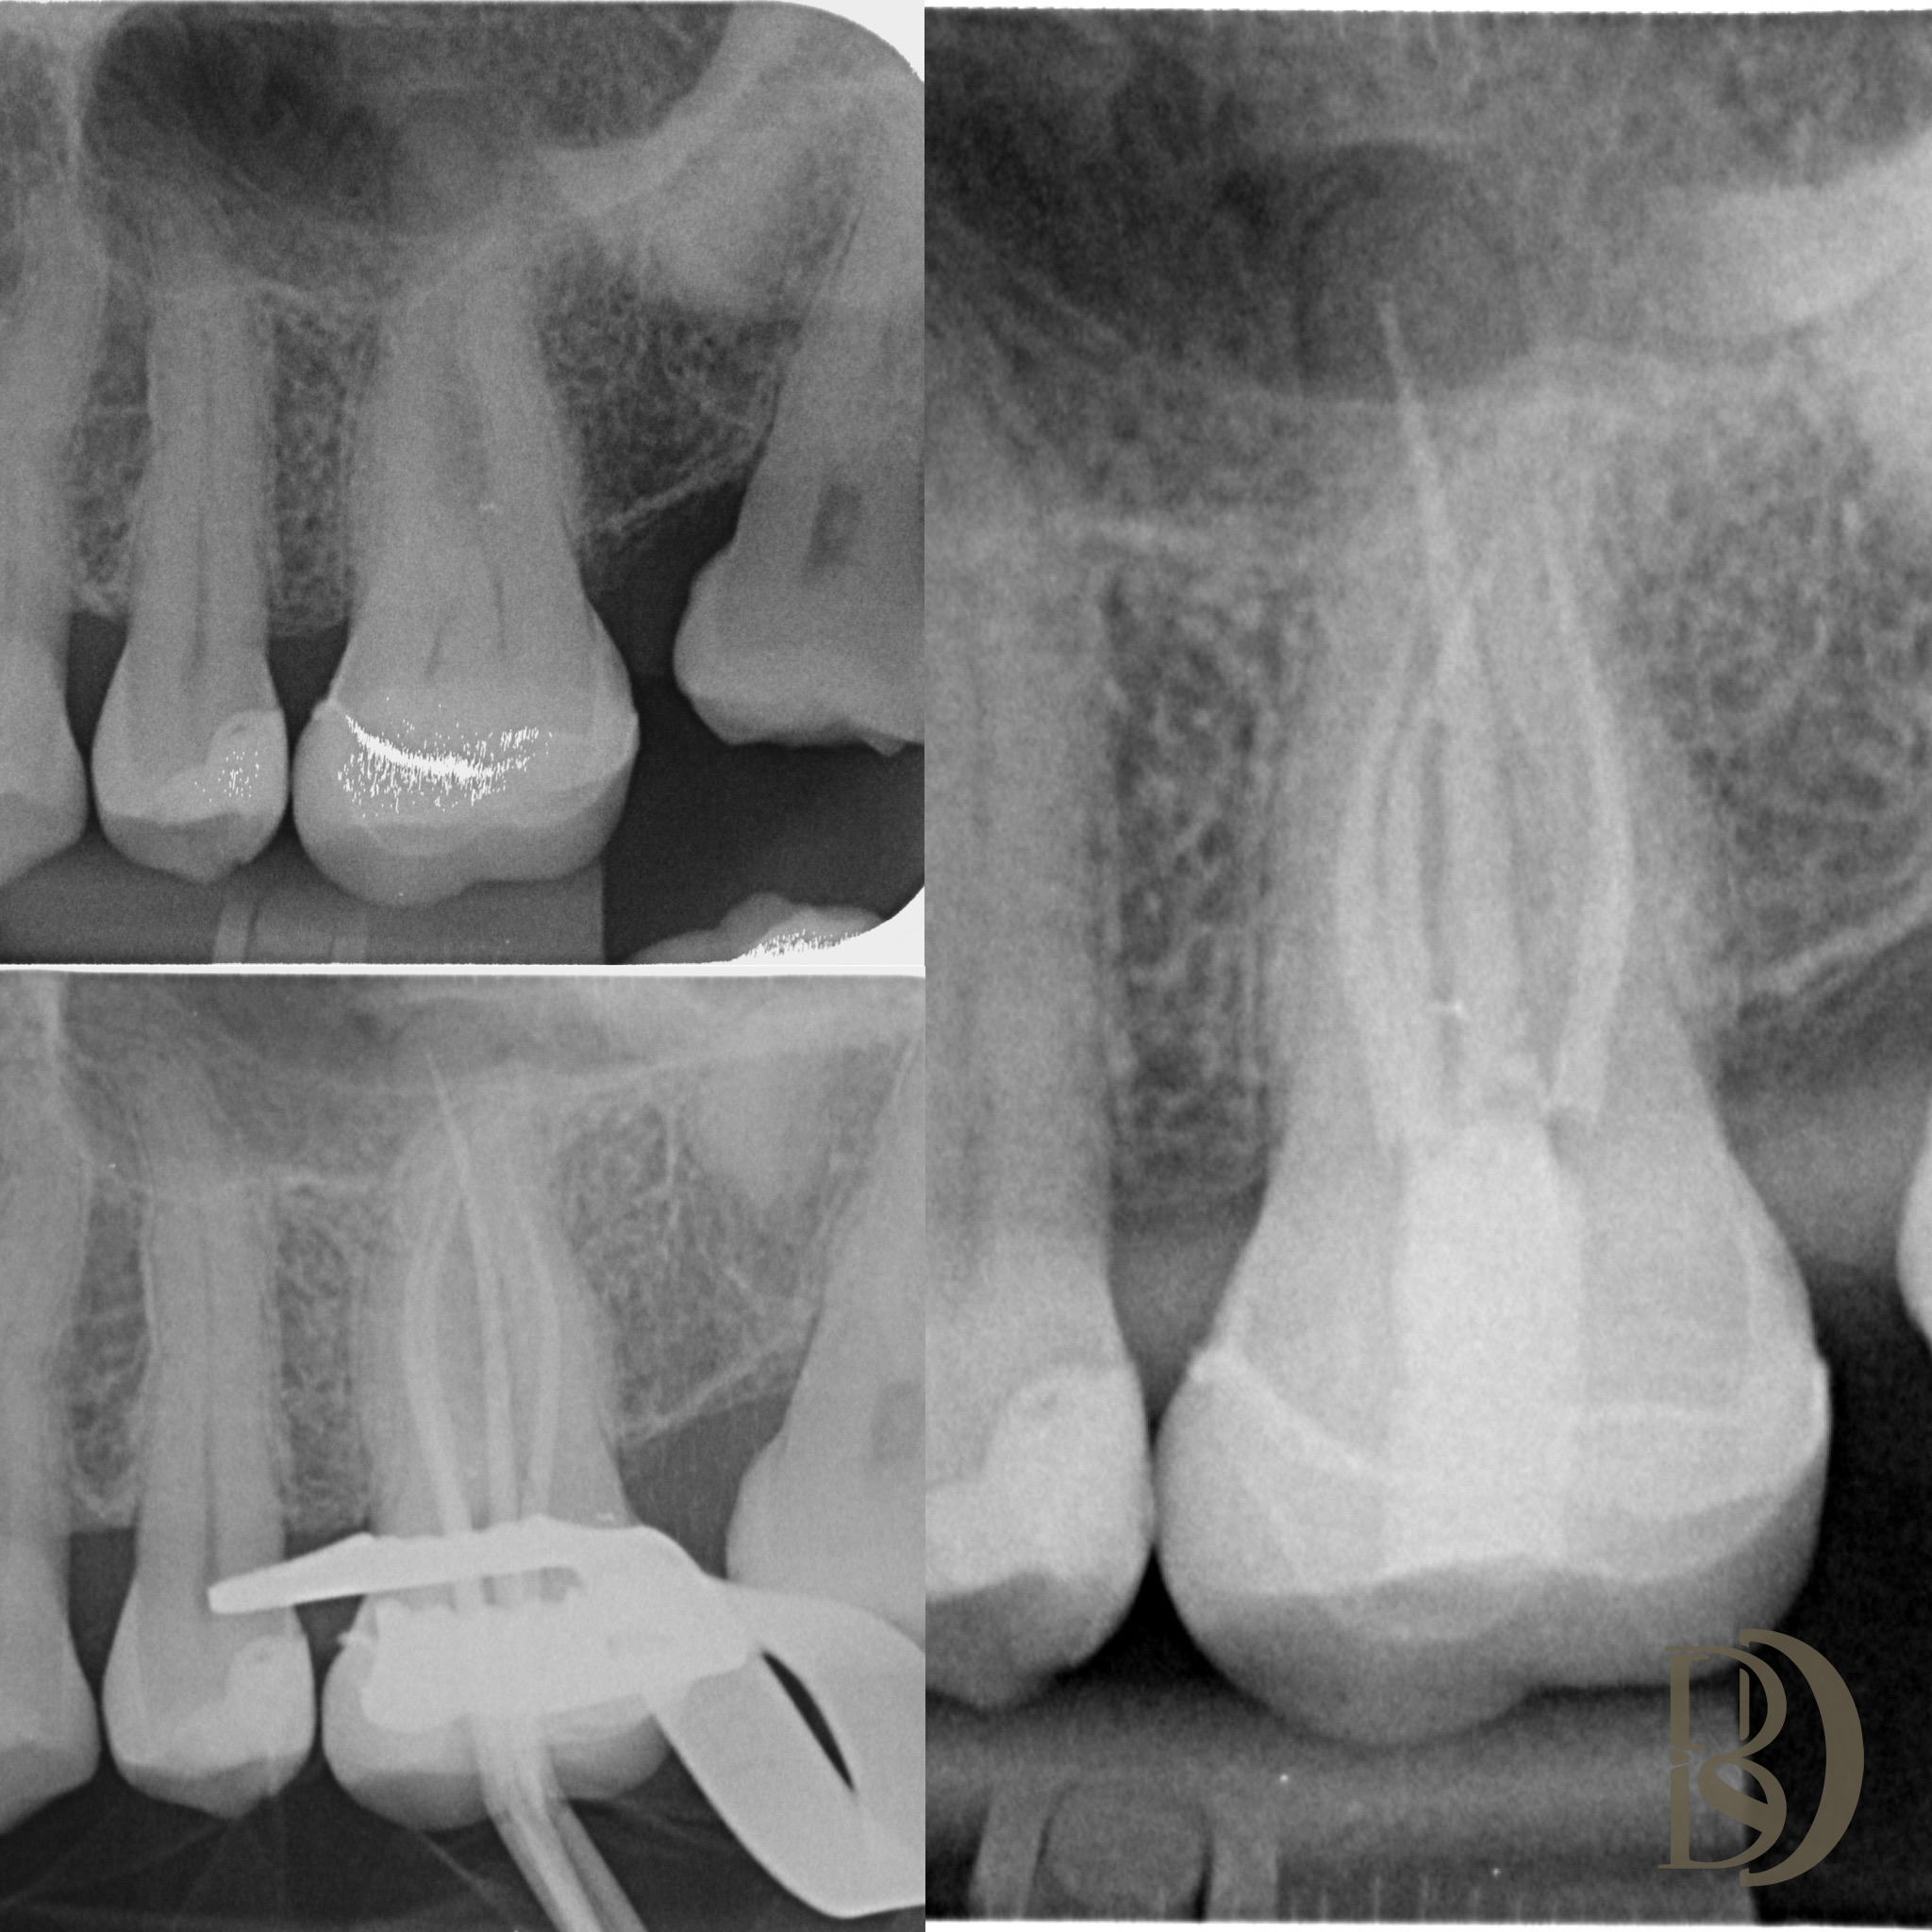

Some examples of Dr Fred’s Endodontic cases:

Dental X-rays displaying teeth and root canals

Dental X-ray showing teeth with root canals and dental crowns.